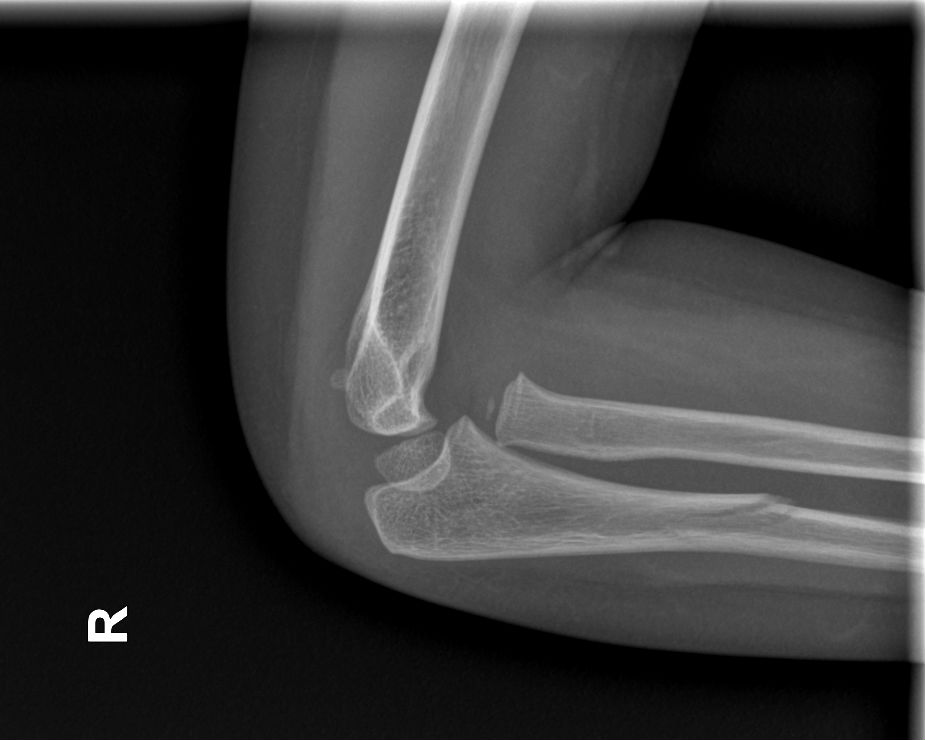

Fig. 1. Radiografía lateral del codo derecho que permite establecer el diagnóstico.

Niña de 3 años que acude al Servicio de Urgencias Pediátricas por dolor en el antebrazo derecho tras una caída. La madre refiere que no ha habido mecanismo de tracción. Tras la administración de analgesia, la paciente continúa con impotencia funcional y supinación mantenida. Se realiza radiografía de codo derecho, donde se observa la siguiente imagen (Figura 1).